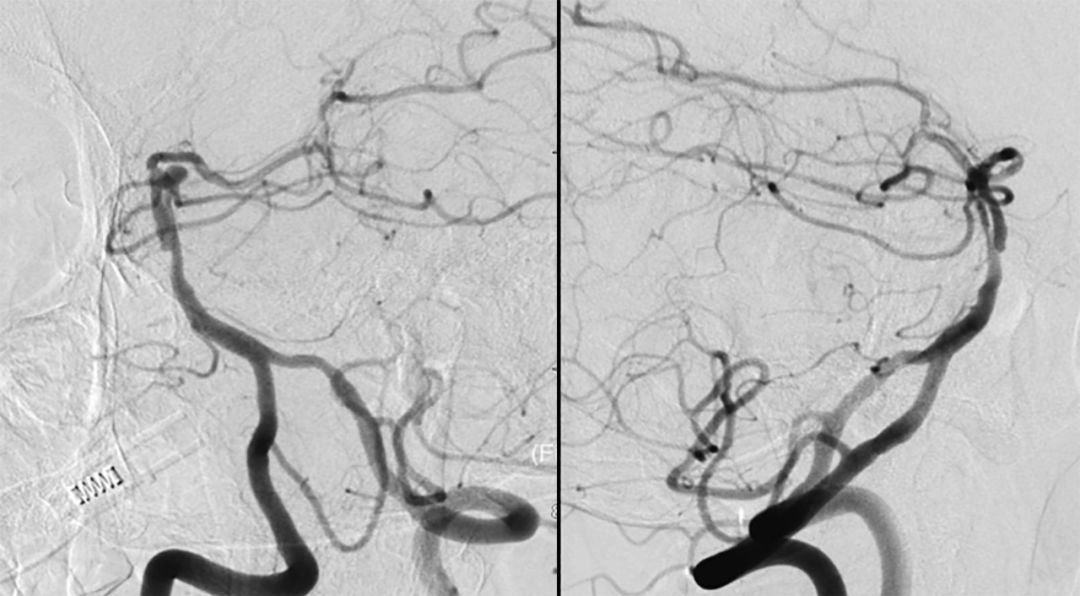

全脑血管造影(本院,2019-8-1 ):基底动脉顶端夹层或者开窗,左侧小脑上动脉瘤(图4)。

图4